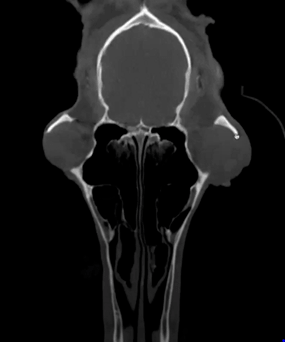

This 14 yo Appaloosa gelding injured his neck. CT images show a subluxation of C2-C4 as well as osteo fragments and compression of the spinal chord.

Featured: JR Lund, University of Wisconsin-Madison